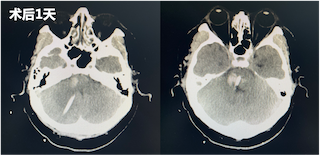

术后第一天,患者仍为浅昏迷状态,但在刺激下可见患者四肢收缩,复查头部CT发现脑干血肿较前明显减少。经神经内科重症监护室医护人员为其制定了专业的诊疗计划,随后团队成员持续术后关注,并向穿刺引流管中注射溶解血肿块的药物。随后,患者逐渐有了意识,对于外界的呼唤有了反应,对外界的刺激产生了回应。